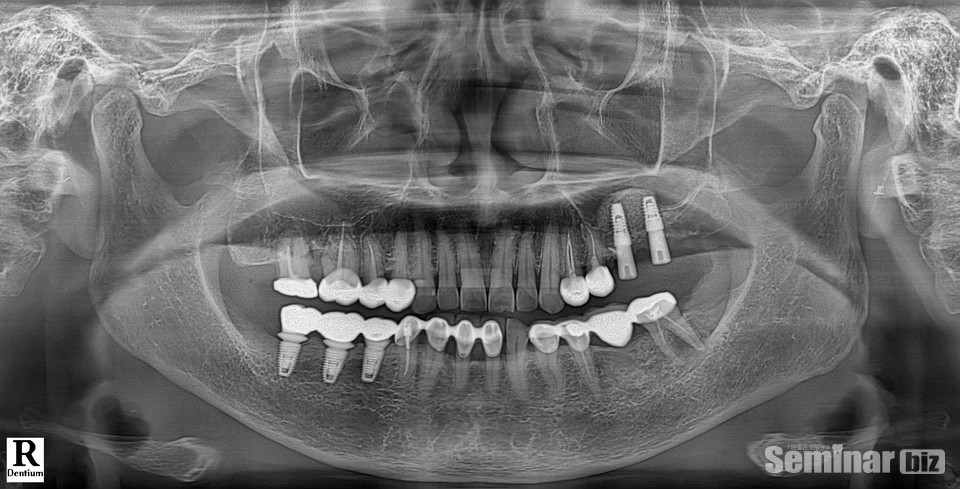

최신 MAR(Metal Artifact Reduction) 알고리즘이 적용된 ‘bright CT’는 금속성 물질이 일으키는 아티팩트를 최소화하여 금속 소재 보철물이 있는 어느 부위든 그 형태와 조직을 선명하게 보여주는 점이 특징이다.

CT 데이터와 스캔데이터(STL)의 병합 시 메탈 번짐으로 영상처리에 어려움이 있지만 ‘bri ght CT’는 이를 최소화했다.

파노라마 촬영 시 Auto Focus Panoramic 알고리즘을 적용해 선명한 전치부 영상뿐만 아니라 진단에 최적화된 이미지를 제공하기 때문에 환자와의 상담 시 설명하기에 매우 편리하다. 인공 음영 Zero, 임플란트 나사선까지도 세밀하게 확인이 가능하다.